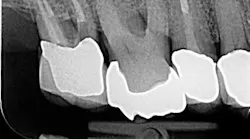

I then employ two instruments—the 30/02 Shaper and the 30/04 Finisher (Tango-Endo, EDS) that are also used in a 30-degree to 45-degree reciprocating handpiece, but designed with a more efficient flute design—to remove tissue and shave dentin away in the longer bucco-lingual isthmuses that may be present. These instruments are also highly resistant to separation, but for caution I suggest limiting their use to three teeth. Generally, there is little need to instrument the canals with larger instruments. If, in fact, the canal is wider than the instrument mesio-distally, in the same way the instruments can broaden the preparation bucco-lingually. It will also accomplish this task in the mesio-distal plane. Once shaped to these dimensions, the canal is properly sealed flooding the canal with epoxy resin cement via a bidirectional spiral applicator and the placement of a single Tango-Endo gutta-percha point (figures 2-3), demonstrated in the before-and-after radiographs.